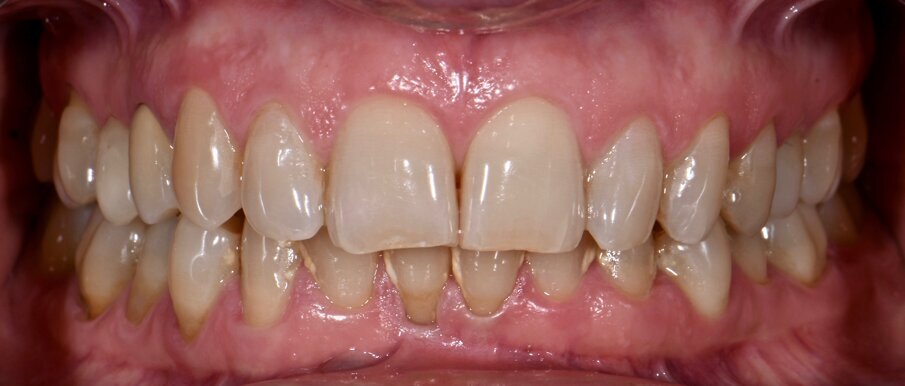

Materiali e metodi Case report Il presente case report è stato redatto in accordo con il CARE checklist (https://www.carestatement.org/checklist, consultato il 29 Gennaio 2024). Una paziente italiana di 44 anni, non fumatrice si è recata alla S.C Riabilitazione Orale Protesi Maxillo-Facciale e Implantologia Dentaria della Dental School dell’Università degli Studi di Torino nel mese di Gennaio 2023, lamentando sanguinamento gengivale durante lo spazzolamento. La paziente ha firmato un consenso informato. L’anamnesi medica della paziente non era rilevante. All’esame intraorale si evidenziava una scarsa igiene orale e la presenza di impianti in sito 15 e 25 (Figg. 1a-1c). I parametri parodontali al baseline sono stati riportati in Figura 2.

Fig. 1a - Condizione clinica al baseline: visione frontale.

Il Full Mouth Plaque Score (FMPS) era 71%, il Full Mouth Bleeding Score (FMBS) era 24% ed è stata osservata una profondità di sondaggio ≥ 4 mm nel 9,5% dei siti, localizzata a livello dei molari e premolari di entrambe le arcate. L’impianto in situ 15 (Nobel Replace, diametro 4,3mm, lunghezza 13mm) e l’impianto in situ 25 (Sweden & Martina SYRA, diametro 4,25 mm, lunghezza 1 mm) presentavano placca e una mucosa peri-implantare eritematosa ed edematosa. Per ciò che concerne l’impianto 15, si era riscontrata una moderata (PPD 4-5 mm) e severa (PPD≥ 6 mm) profondità di sondaggio, con una profondità media di 3.33 mm. FMBS e FMPS erano del 100%, così come riportato in Figura 2. La rilevazione dei parametri peri-implantari dell’impianto 25 aveva evidenziato PPD moderati nel 67% dei siti e una PPD severa a livello mesio-vestibolare. FMPS e FMBS erano 100%.